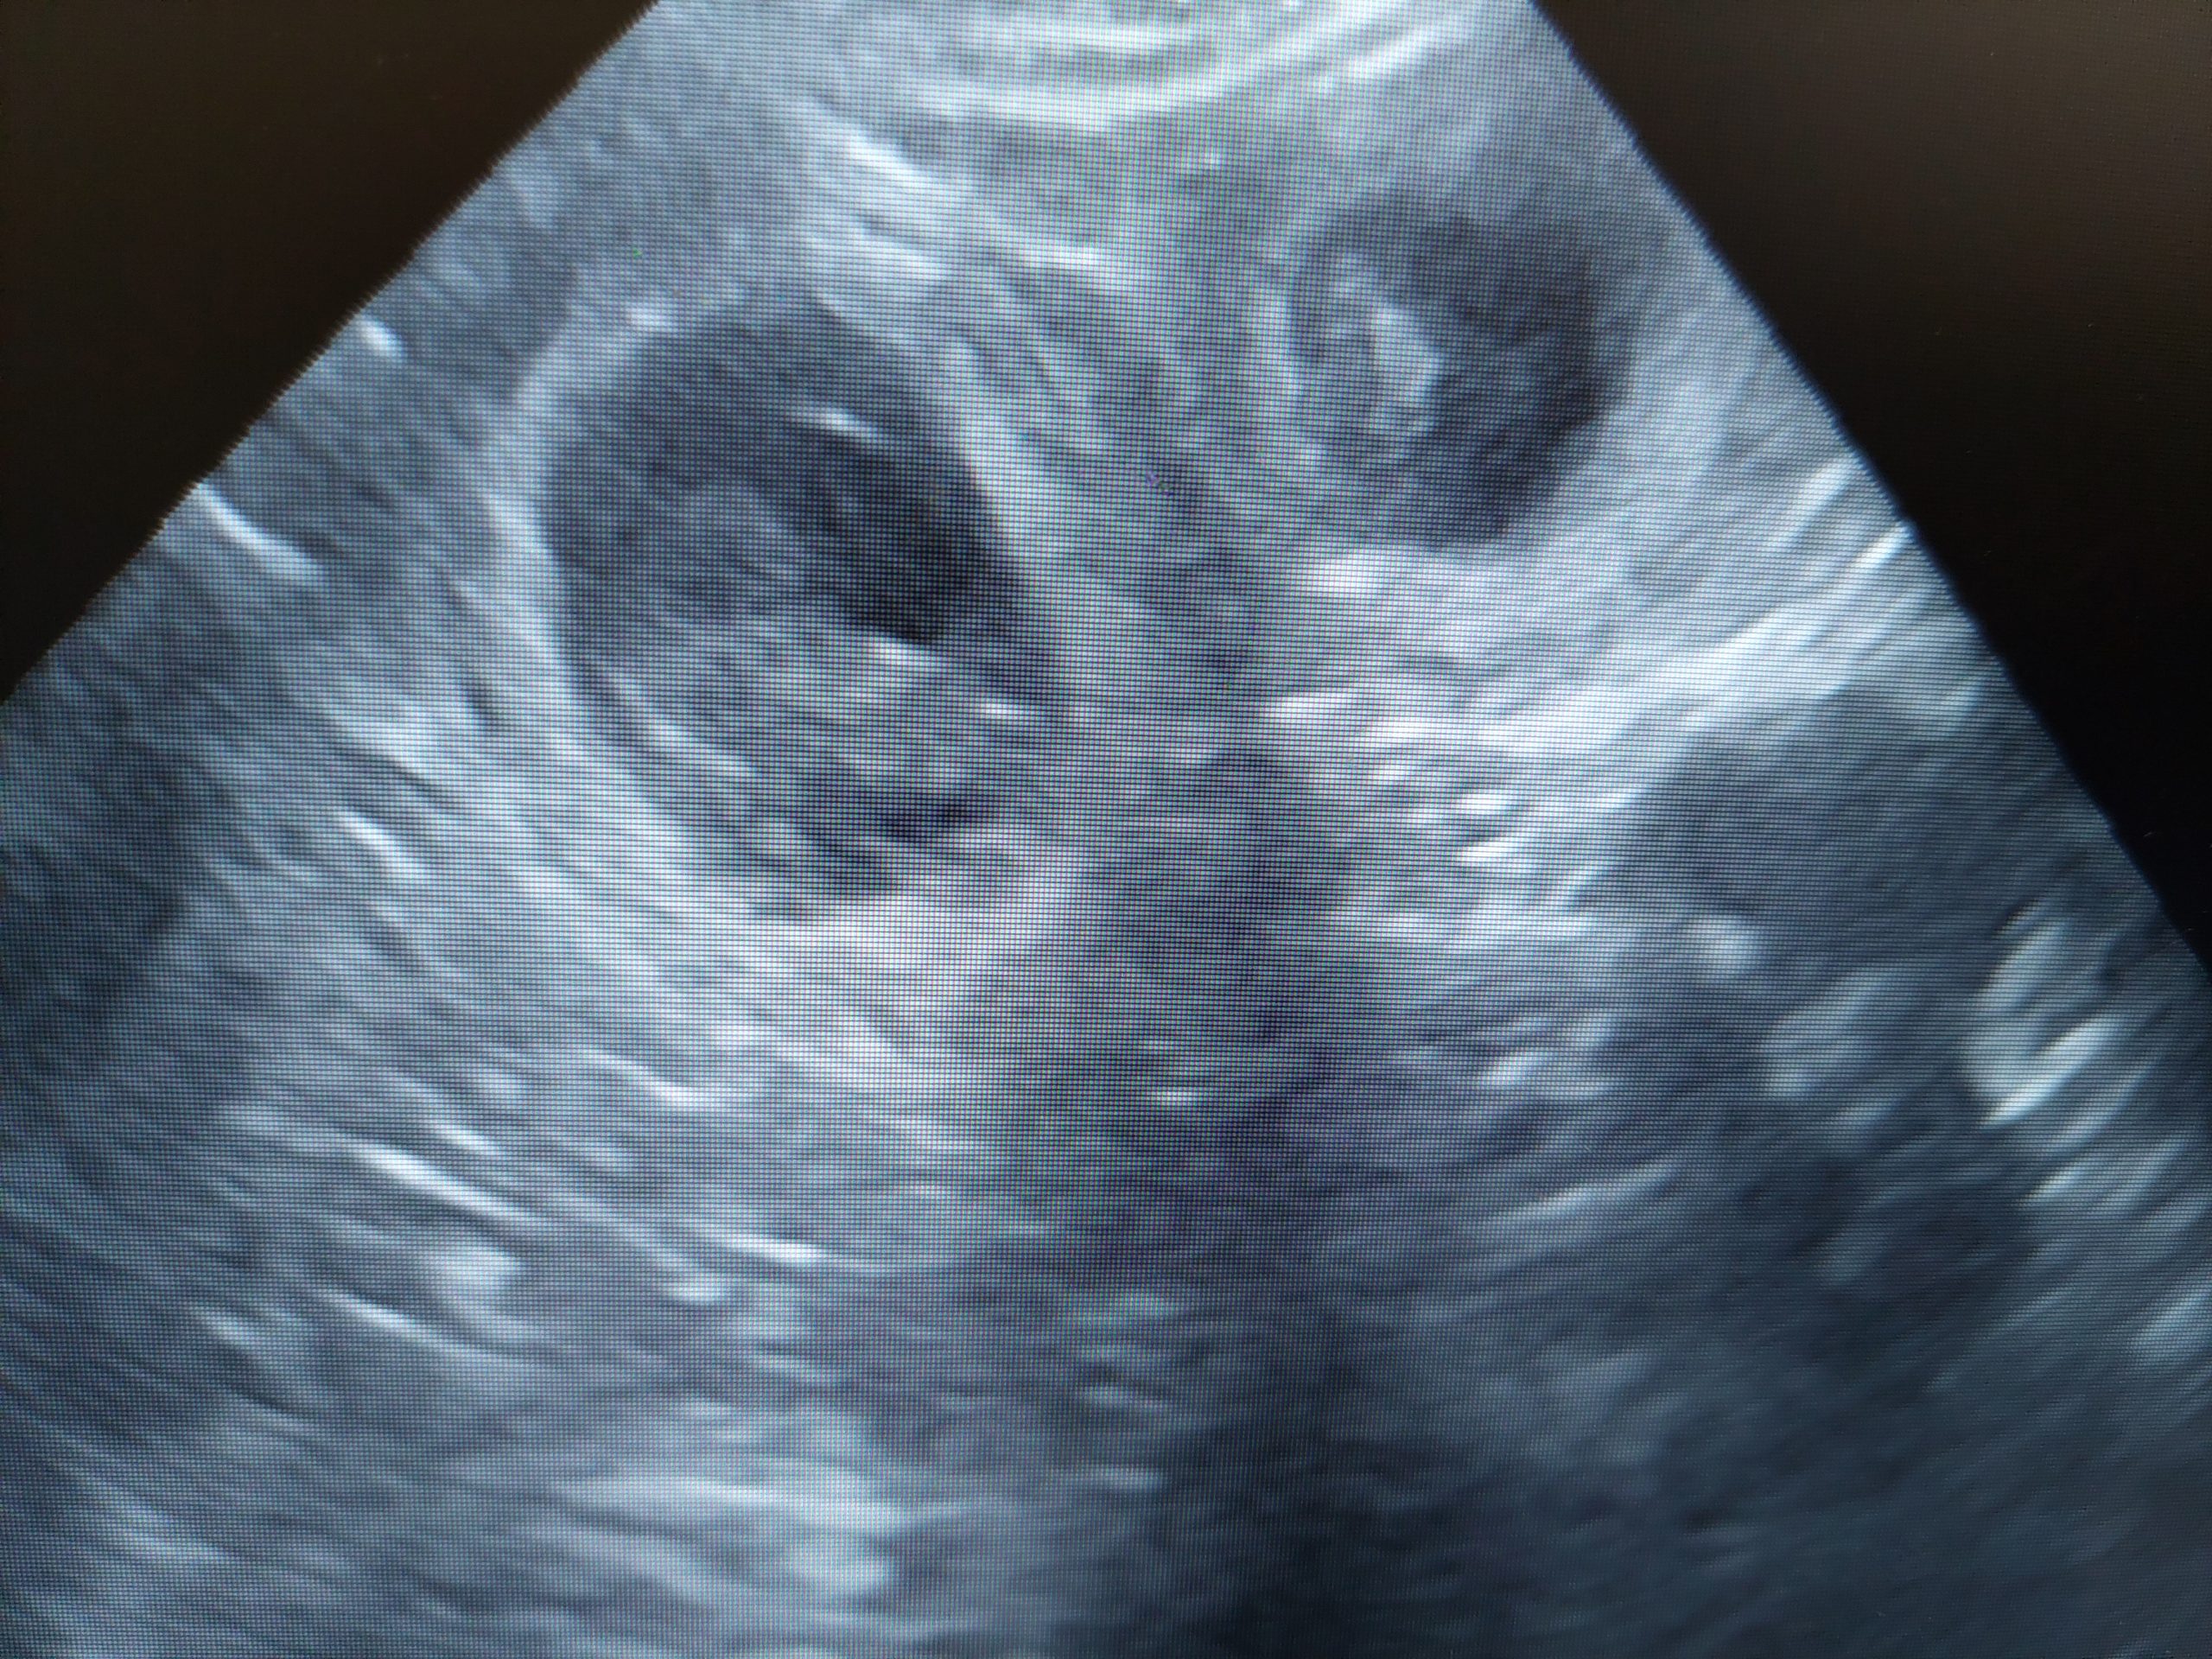

Bayerischer Gebirgsschweisshunden puppies born 19/08/2022. 3 males en 4 females. Mother Pleun (Bernis Van Jagthuis Gerven) and father Abe ( Swawir Sfora Nemroda) regularly used for tracking owned by Herwi Hoenink kennel Van t’Rutbekerveld. All puppies have a new owner.